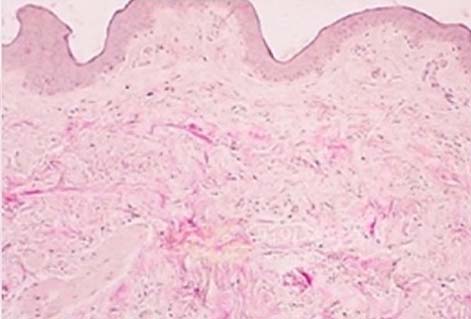

콜라겐 섬유의 밀도와 구조가 개선된 것을 확인할 수 있습니다.

시술전

시술 30일 후